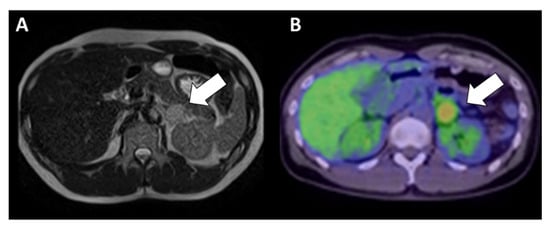

2. Case Presentation